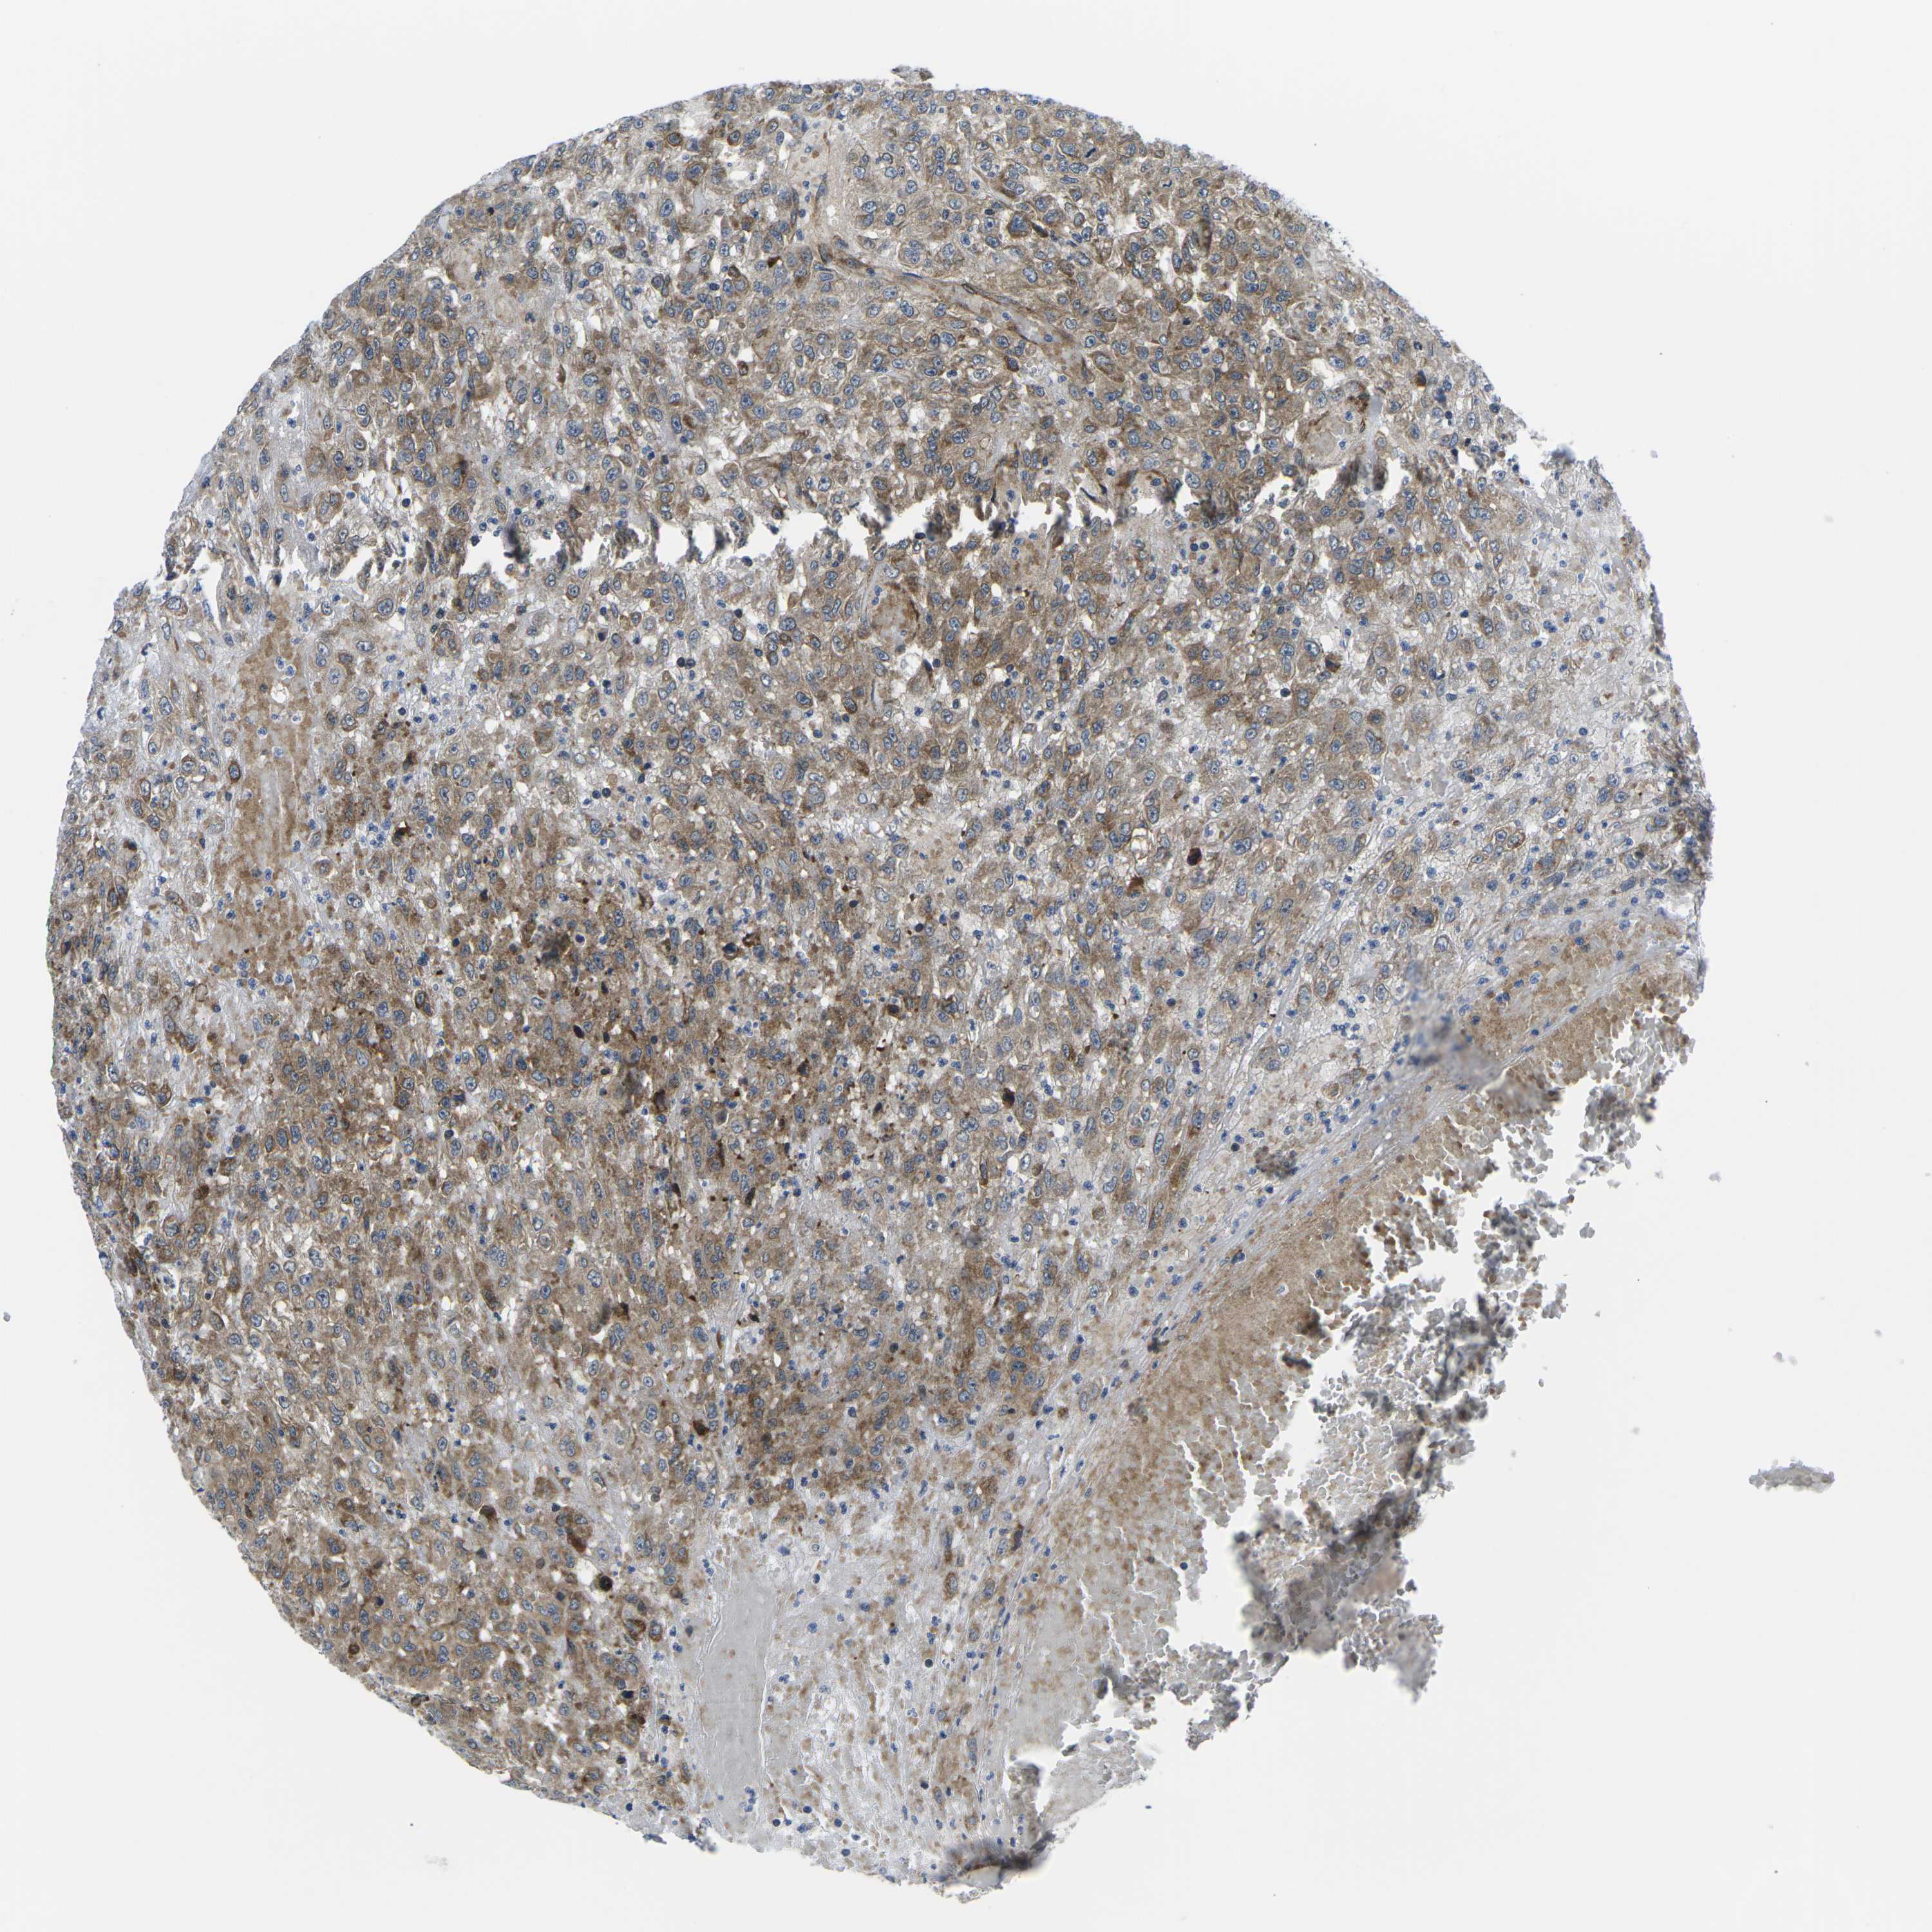

UROTHELIAL CANCER - Protein expressioni

A mouse-over function shows sample information and annotation data. Click on an image to view it in a full screen mode. Samples can be filtered based on level of antibody staining by selecting one or several of the following categories: high, medium, low and not detected. The assay and annotation is described here.

Antibody stainingi

Antibody staining in the annotated cell types in the current human tissue is reported as not detected, low, medium, or high, based on conventional immunohistochemistry profiling in selected tissues. This score is based on the combination of the staining intensity and fraction of stained cells.

Each image is clickable and will lead to virtual microscopy that enables deeper exploration of all samples and also displays staining intensity scores, fraction scores and subcellular localization as well as patient and tissue information for each sample.

Antibody CAB004077

Urothelial carcinoma, High grade